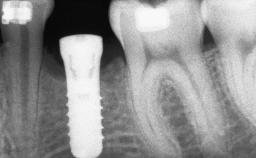

Bone Augmentation Staged|Vertical

Augmentation Materials Autogenous chips|Membrane

Bone Volume Deficient vertically or deficient vertically AND horizontally